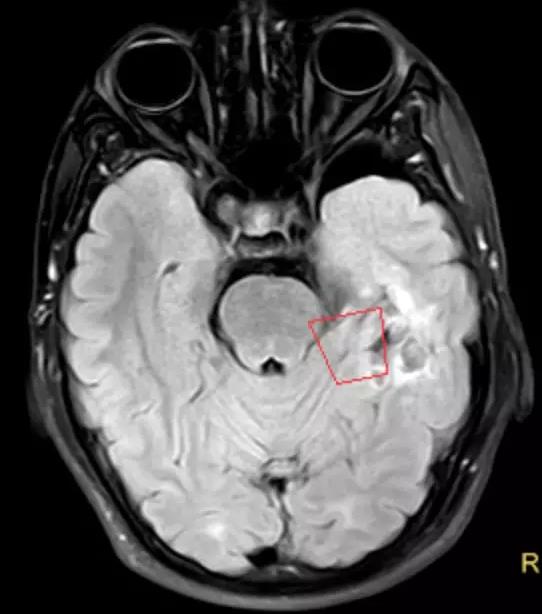

23岁的小李(化名)一直在南方打工,通过自己的努力承包了一个快递点,当上了小老板。然而,他却在自己事业有成的时候患上了癫痫,每次发作都要持续三五分钟。在南方某医院检查后诊断为脑瘤引起的,这可吓坏了小李。为了更好的治病,家里人带着他找到了付旭东主任。通过进一步的检查以及长程视频脑电监测,考虑左侧叶低级别胶质瘤合并继发性癫痫(图1)。付旭东主任及其团队为小李制定了一个详尽的手术方案,术中监测确定癫痫病灶并切除肿瘤,术后再次监测确保癫痫灶切除彻底。在麻醉科及癫痫定位室医务团队的配合下,手术进行的很顺利,切除脑肿瘤的同时也切除了癫痫病灶,一举两得。

图1 红框所示左颞叶病变,考虑低级别胶质瘤